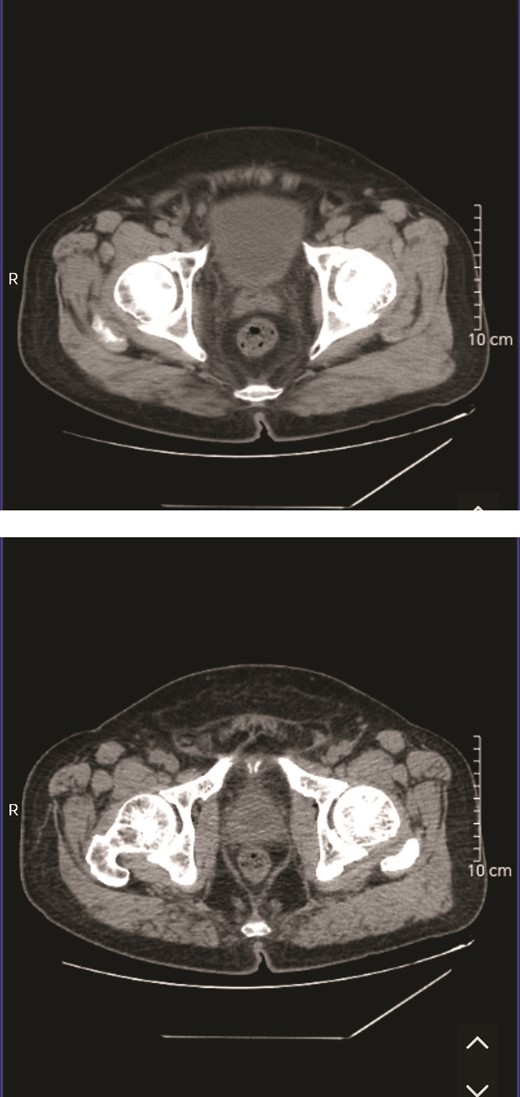

Auxiliary examination: Complete blood count results upon admission revealed postoperative hematologic inflammation indicators (Fig. 1); procalcitonin: 0.080 ng/ml; prostate tumor marker: 1.66 μg/L; Urinalysis indicated glucose: 1+, occult blood: 3+, protein: +−, and leukocytes: 2+; quantitative urine sediment analysis showed urine red blood cells: 115/μl, urine white blood cells: 118/μl, and urine white blood cell clumps: 7/μl; Urine culture showed no growth of organisms; Bladder residual urine volume ~655 ml; Urinary system ultrasound shows prostate hyperplasia with calcification (size: 5.0 × 3.6 × 3.8 cm); The CT scan results indicated prostate hyperplasia, with MRI recommended if deemed necessary (Fig. 2).

The CT scan results indicated prostate hyperplasia, with MRI recommended if deemed necessary.

The patient’s CT suggests prostate hyperplasia, with a suggestion to consider MRI if deemed necessary. Timely completion of prostate MRI and transrectal ultrasound examinations could potentially facilitate early detection of abscesses, enabling prompt intervention. Early identification plays a pivotal role in the effective management of prostate abscesses [8].